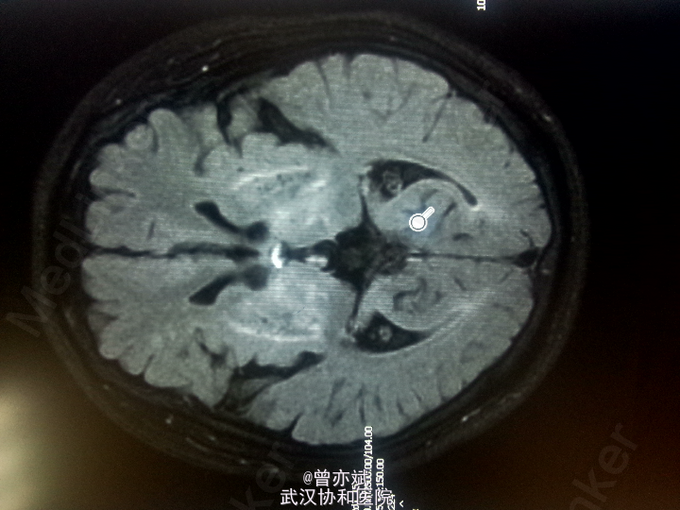

查体:T 36.4℃,P 77次/分,R 20次/分,BP 110/70mmHg。神志清楚,查体合作,皮肤及全身浅表淋巴结未及肿大,心肺腹未及明显异常,双下肢无水肿,生理反射存在,病理反射未引出。 专科查体:神清,吐词不清,语速减慢。双侧角膜可见K-F环,颅神经(-),四肢肌力正常,肌张力减低,左上肢不自主运动,姿势性震颤明显,腱反射对称性活跃,病理征未引出。感觉系统无异常。左手指鼻试验不准。Kernig征阴性。 辅助检查:血常规、尿常规、大便常规、大生化、ENA、ANCA、甲功五项、类风湿三项均阴性,铜蓝蛋白小于20mg/L(正常值220-580mg/L),叶酸、VitB12均正常。MRI平扫+增强 双侧基底节、丘脑、中脑及桥脑、双侧齿状核稍长T1稍高FLAIR信号及双侧苍白球、壳核及黑质信号改变,结合病史考虑肝豆状核变性;脑萎缩,尤以小脑桥脑明显。